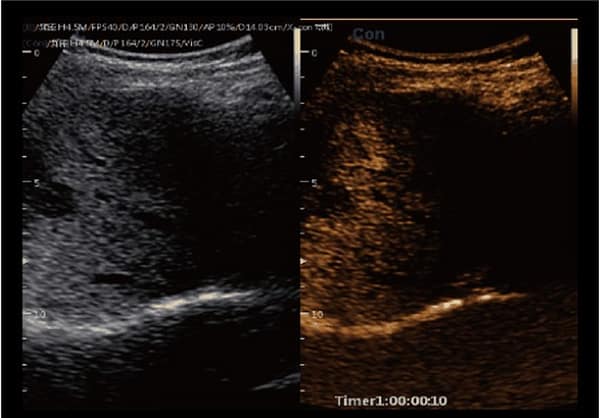

– Nó có khả năng chụp ảnh đa phương thức cùng với nhiều chức năng tự động như SonoColor , SonoCrystal , SonoAI-OB, Intelligent doppler, Sonocontrast , SonoNeedle , Color toàn cảnh , Dữ liệu thô …

- SonoColor và SonoContrast: Cung cấp phân tích dòng định lượng và độ nhạy cao hơn, thích ứng với mọi loại đầu dò.